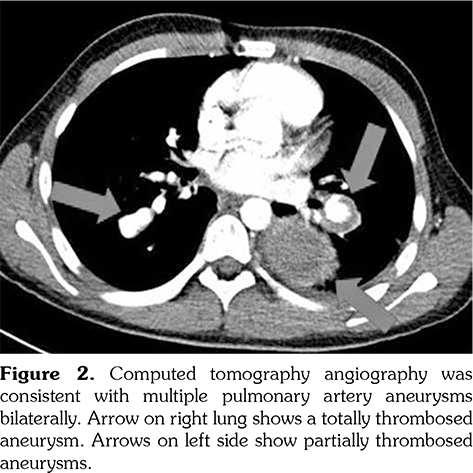

Chest X-ray showed retrocardiac hyperdensity on admission (Figure 1). Diagnostic investigations for tuberculosis were all negative. On bronchoscopy; left lower lobe bronchus was narrowed due to the external compression and abundant viscous secretions were observed. Computed tomography (CT) angiography was performed, which was consistent with multiple PAAs bilaterally (Figure 2). Diagnostic investigations such as echocardiogram and lower extremity venous Doppler ultrasonography, renal function evaluation, eye examination, abdominal ultrasound, and rheumatologic tests revealed no pathological findings. Our patient’s investigational tests for PAA were negative for cardiovascular disease, pulmonary hypertension or any infection.

Pathergy test was performed due to the presence of recurrent oral and genital ulcers, supporting the diagnosis of BD. Pathergy test was positive and he was diagnosed as BD according to the history, physical examination and laboratory findings. Monthly intravenous cyclophosphamide pulses combined with high dose methyl-prednisone were initiated and followed by prednisolone 2 mg/kg/day. Afterwards, left lower lobectomy was performed. Pathological examination revealed PAA with thrombus in the lumen, fibrosis and lymphoplasmacytic inflammatory cell infiltration adjacent to small- and medium- sized vessels (Figure 3). He was clinically well after lobectomy and admitted for the second pulse immunosuppressive therapy. Meanwhile, CT angiography was performed to evaluate the aneurysm at the right lower lobe which showed regression of PAA from 16 mm to 6 mm in diameter. Endovascular embolization was planned for the right lower lobe PAA. However, unfortunately, he presented with massive hemoptysis five days later. The patient passed away with massive hemoptysis originating from the right lower lobe PAA.